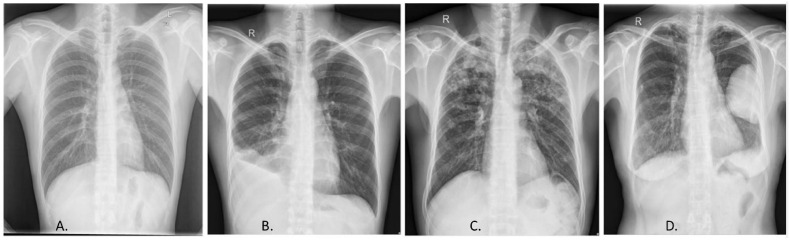

Patients suffering from tuberculosis experience severe cough with blood in the sputum, and develop severe complications such as emphysema, distortion of the bronchioles, thickening of the pleural membrane, etc. In order to investigate the unexplained cough or study the involvement of the extra-thoracic cavity, a chest X-ray is often the primary test. Chest X-ray helps in a comprehensive assessment of the lungs and the pleural membrane (Fig. 5 ) [40,41]. Computed Tomography is a significant tool to assess the complexity of the disease by evaluating the formation of lesions, pleural effusion, and transient thickening of the lobular septa. It aids to differentiate the etiologies of TB from pneumonia [40,42,43]. The lesions are detected in patients with active TB infection; they disappear within 5–9 months after treatment. In case of reactivation of the disease, these lesions were observed followed by fibrosis. Hence CT test can provide valuable evidence of the progression of the disease especially if there is a chance of relapse [40,44].

Fig. 5.

Radiological diagnosis of TB, Chest X-ray. (A) Normal chest X-ray. X-ray displaying different manifestations of TB, (B) pleural effusion, (C) infiltrates, (D) cavity lung lesion. Reprinted from (Ayaz et al., 2021) (open access).